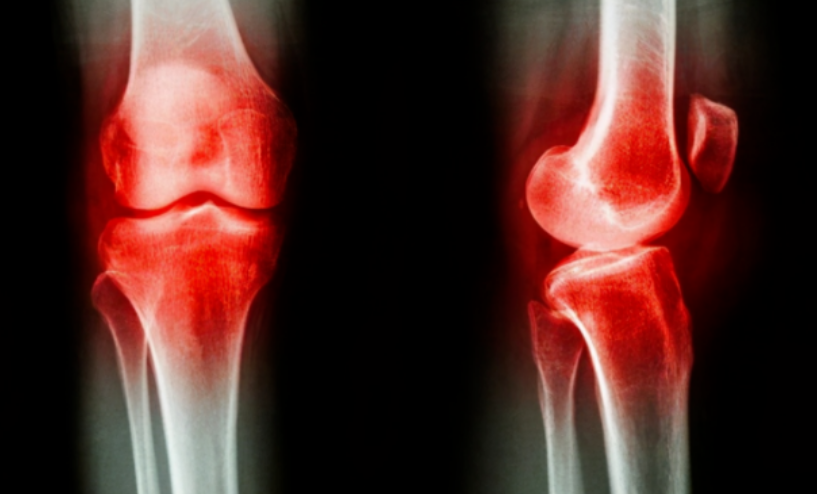

痛風在臨牀上其實就是關節性疾病的一種,它是以高尿酸血癥作為基礎而出現的關節病。當患者體內尿酸代謝和生存出現障礙後,大量尿酸就會在體內生成、並析出一種名為尿酸鹽結晶的物質,它可堆積在患者的各個關節處。

越是皮膚覆蓋薄弱的關節,越是容易堆積結晶。因此,大部分痛風患者在初次發病時,都是出現了腳趾關節異常劇痛、紅腫!